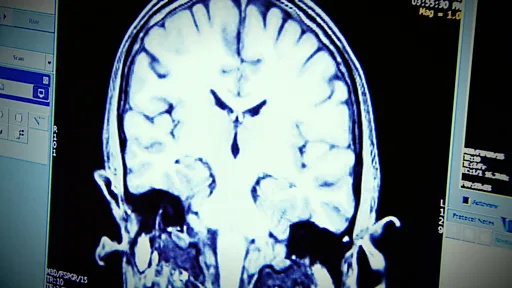

அவரது மண்டை ஓட்டில் காயம் ஏற்பட்டது. பின்னர் இரண்டு மாதங்கள் கோமா நிலையில் இருந்தார். அவரது மூளையில் 10 செ.மீ நீளமும், 4 செ.மீ அகலமும் கொண்ட ஒரு ரத்தக் கட்டு உருவானது.

உணர்வுகளைக் கட்டுப்படுத்தும் மூளையின் முன் பகுதியுடன், உணர்வுகளை வெளிப்படுத்துவத்தைக் கையாளும் சிறு மூளை மற்றும் மூளைத் தண்டு ஆகியவற்றுக்கு இடையே உள்ள இணைப்பு சேதமடையும்போது இந்த நிலை உண்டாகிறது.

நவீன மூளை ஸ்கானர்